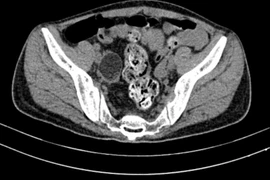

Nhiều bệnh nhân trẻ bị viêm não tự miễn do kháng thể MMDAR liên quan đến u quái buồng trứng. Người bệnh có thể mất đi cơ hội làm mẹ và điều trị hormon sinh học cả đời.

Nữ sinh 22 tuổi co giật liên tục, hôn mê sâu, thở máy ròng rã 2 tháng vì mắc viêm não tự miễn. Viêm não tự do kháng thể kháng thụ thể NMDA chủ yếu gặp ở người nữ trẻ tuổi và thường có liên quan đến các khối u.